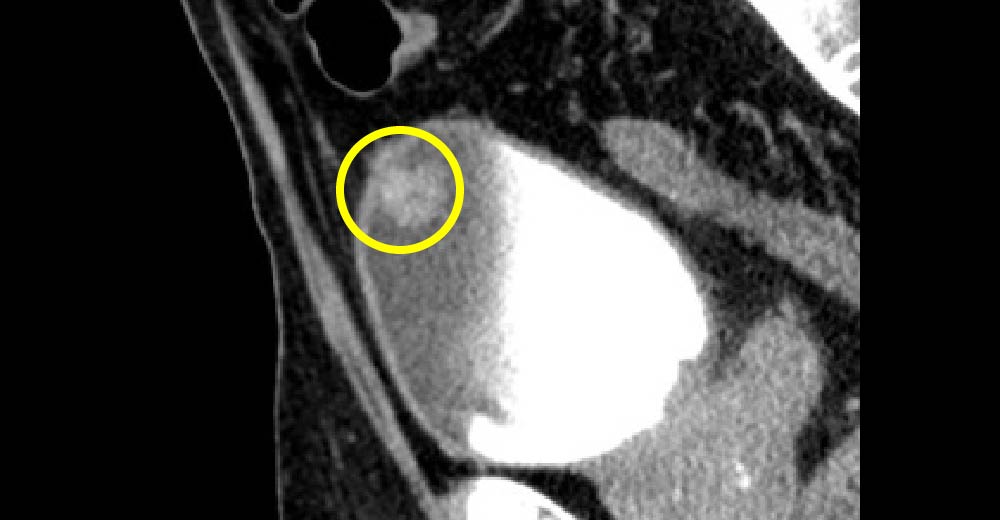

前立腺がん症例です。前立腺生検前にMRI撮影を行っています。

前立腺がん

造影CTにて前立腺に造影効果のある高吸収域が指摘されます。